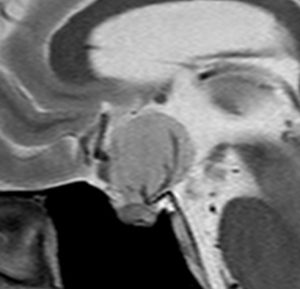

40代の女性に,軽度の両耳側半盲で発生したものです。視交叉と視床下部の下面に腫瘍があり,下垂体柄の位置が全くわからず,下垂体の前葉と後葉は侵されていません。ですから,下垂体柄から発生した腫瘍であり,pituicytomaが強く疑われます。T2ではほぼ等信号,小さなのう胞があり,ガドリニウムで強く増強されます。手術では正常下垂体柄の一部が右側にうすく残っており,幸運にも亜全摘出できて下垂体機能は温存できました。残存腫瘍は増大傾向を示していません。でも,このようなタイプを積極的に摘出すると,汎下垂体機能低下症を招くことが多いので,手術するかどうかの判断はとても難しいです。